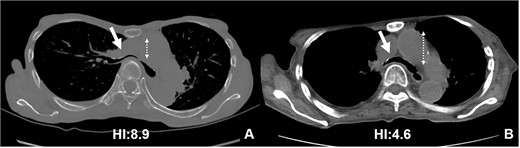

The patient was a 74-year-old woman with a history of childhood PE. Fourteen years ago, a total glossolaryngectomy was performed at another hospital for oropharyngeal cancer, and a permanent tracheal stoma was created. Approximately 2 years later, the patient gradually experienced difficulty in breathing. Chest computed tomography (CT) revealed severe PE and right main bronchial stenosis. Subsequently, the patient was referred to our department. A preoperative spirometry test showed a vital capacity of 1.14 L (45% of the predicted value). As part of the imaging test, a chest CT indicated a leftward deviation of the trachea. Symmetrical depression with a Haller Index (HI) of 8.9 and stenosis of the right main bronchus were observed at the same site (Fig. 1). The chest CT taken over 8 years indicated that the leftward deviation of the trachea had progressed and the thoracic depression had worsened (Fig. 2). Intraluminal observation using a bronchoscopy revealed severe stenosis of the right main bronchus, making peripheral observation challenging (Fig. 4A).

Chest CT findings of severe PE with stenosis of the right main bronchus. The right main bronchus was severely narrowed with a HI (HI) of 8.9 (arrow).